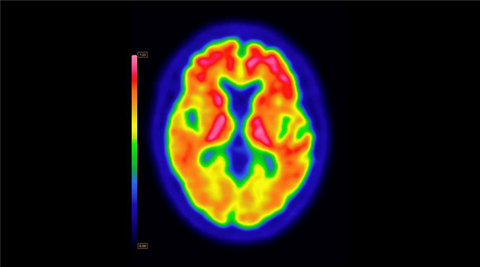

PET brain scan using Vizamyl (flutemetamol F18) with quantification software

Up to now, amyloid diagnostics such as Vizamyl have been used to provide a visual assessment of amyloid plaque accumulation in the brain. With quantification now added to the label, clinicians can reach a more objective assessment, using software that enables a calculation of amyloid load, with published research demonstrating that quantification improves diagnostic confidence and consistency among readers1,2,3. In addition, with the removal of a limitation of use for monitoring therapy effectiveness, Vizamyl can also now be used to assess whether the level of amyloid plaques has been reduced sufficiently for the therapy to potentially be stopped.